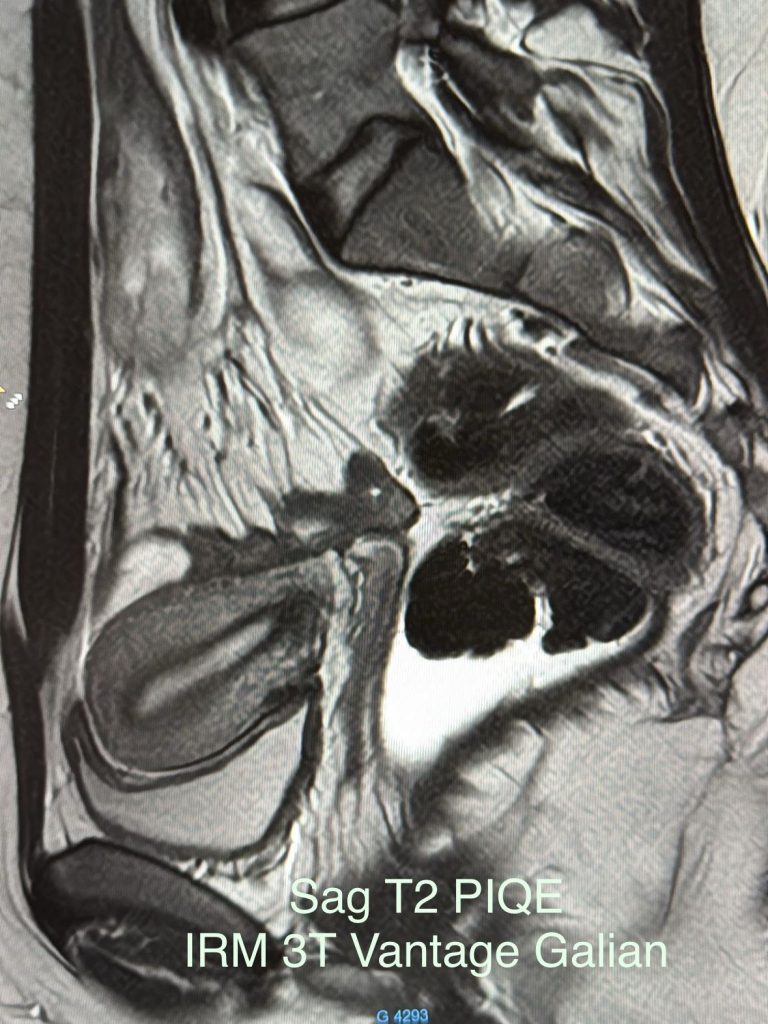

IRM CANON 3T

Première nationale. Installation de la toute première Irm 3T Vantage Galan suprême Canon sur notre site à l’hôpital des Massues🚨🚨